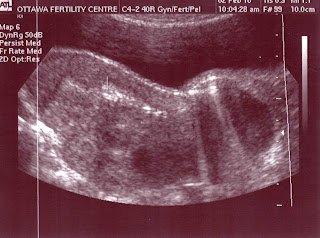

The transfer itself was quick and exciting. The nurse made sure I was comfortable and talked me though everything I was seeing on the sceen. The sonographer held the ultrasound probe on my belly so I could see my uterus clearly. The embryologist who had made the magic happen with our egg and sperm explained the blastocysts in detail. The doctor inserted the speculum and the catheter and dropped off our 2 little blasts into my uterus. My husband stared at the monitor with me while holding my hand. Of course this is not the way anyone imagines conception to happen. We were supposed to go to a party, get a bit tipsy, make love only to discover we were pregnant 2 weeks later. If there is one thing I have learned by now, it is that it doesn't matter how we get there, just that we know we will. As for me, I cried during the transfer. I cried when I saw the 2 tiny air bubbles on the screen which they explained were my 2 blasts entering my uterus. It was the happiest moment. I am Pregnant until Prove Otherwise.

Here is a picture of my little blasts being dropped off. You cannot actually see them but the sonographer put an arrow to show where they are. What a beautiful picture.